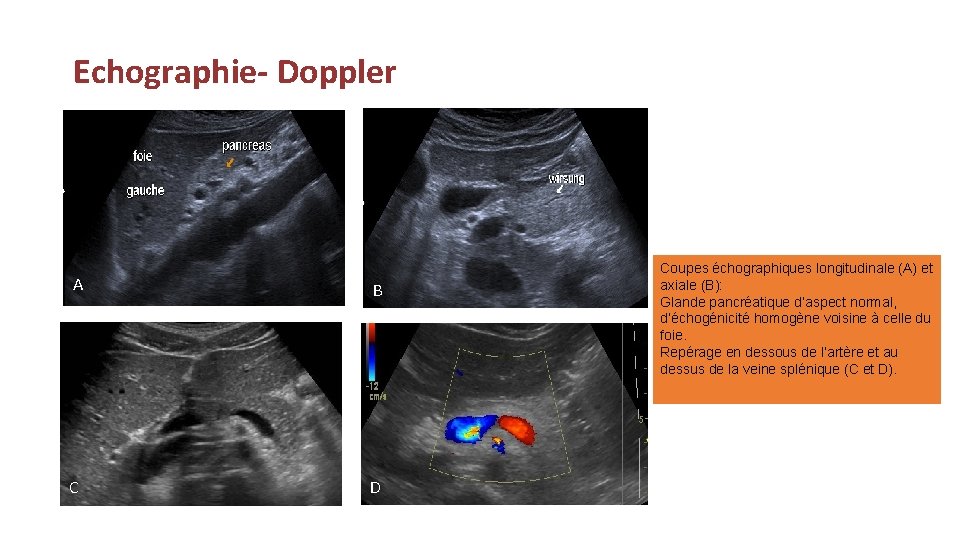

Echographie- Doppler § Examen rapide, accessible et anodin. § Parenchyme pancréatique homogène, composé d’échos fins et réguliers, d’échogénicité voisine ou discrètement plus hyperéchogène que celle du foie normal chez l’adulte. § Chez l’enfant, il apparait hypoéchogène que le foie. § Doppler: étude des vaisseaux péri pancréatiques, rarement suffisant pour un bilan d’extension local précis. § Reste en revanche essentielle pour la recherche de lithiase vésiculaire dans les pancréatites aiguës d’origine lithiasique.

Echographie- Doppler A B C D Coupes échographiques longitudinale (A) et axiale (B): Glande pancréatique d’aspect normal, d’échogénicité homogène voisine à celle du foie. Repérage en dessous de l’artère et au dessus de la veine splénique (C et D).